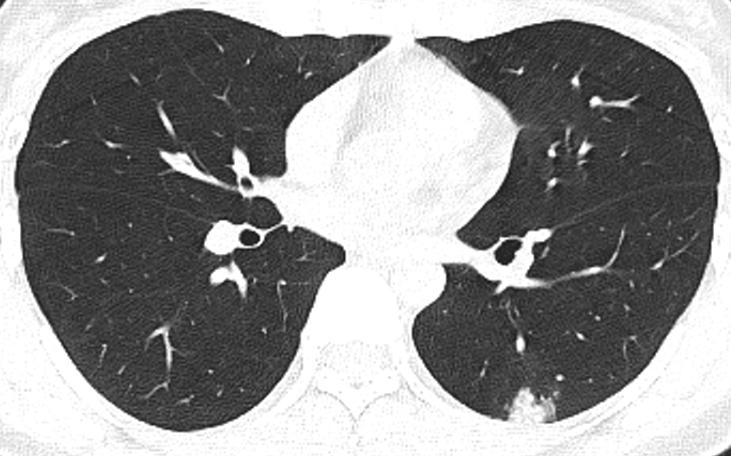

胸部CT示:双肺多发磨玻璃结节,左下叶背段散在实性结节,散在小空洞,部分支气管的管壁增厚,如下(图1~17)。